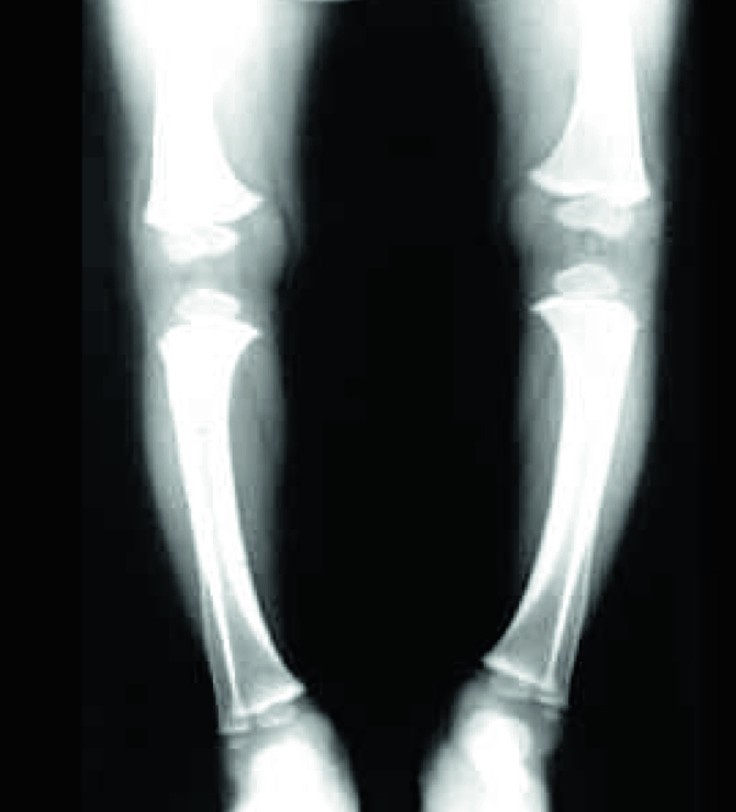

Rahhiit algab hiilivalt. Laps muutub virilaks, pahuraks, tema uni on häiritud ja rahutu. Kui laps magab või imeb, hakkab ta pea higistama, laps hõõrub kukalt vastu madratsit, mistõttu hõõrumiskohalt kaovad juuksed. Seejärel tekivad muutused luustikus, suure lõgeme servad muutuvad vetruvaks, kuklaluudes tekib koldeline pehmenemine ning kolju muutub ebasümmeetriliseks. Toruluude kasvupiirkondade kõhredesse tekivad paksendid. Vaagnaluud moonduvad, tekivad X- või O-jalad. Rindkere muutused hõlmavad roideid: roiete kõhre- ja luuosa piirile tekivad paksendid, mis üheskoos meenutavad palvekeed (nn rahhiitiline roosikrants); roided on kinnituskohtadelt sissepoole tõmbunud, tekitades sinna vao, rinnak võib kiiluna ettepoole ulatuda (kanarind). Hammaste lõikumine hilineb ning võivad esineda hambaemaili defektid. Lapse lihaste toonus alaneb, tekib punnkõht, motoorne areng peetub.

Rahhiidi tagajärjel moondunud luustik.